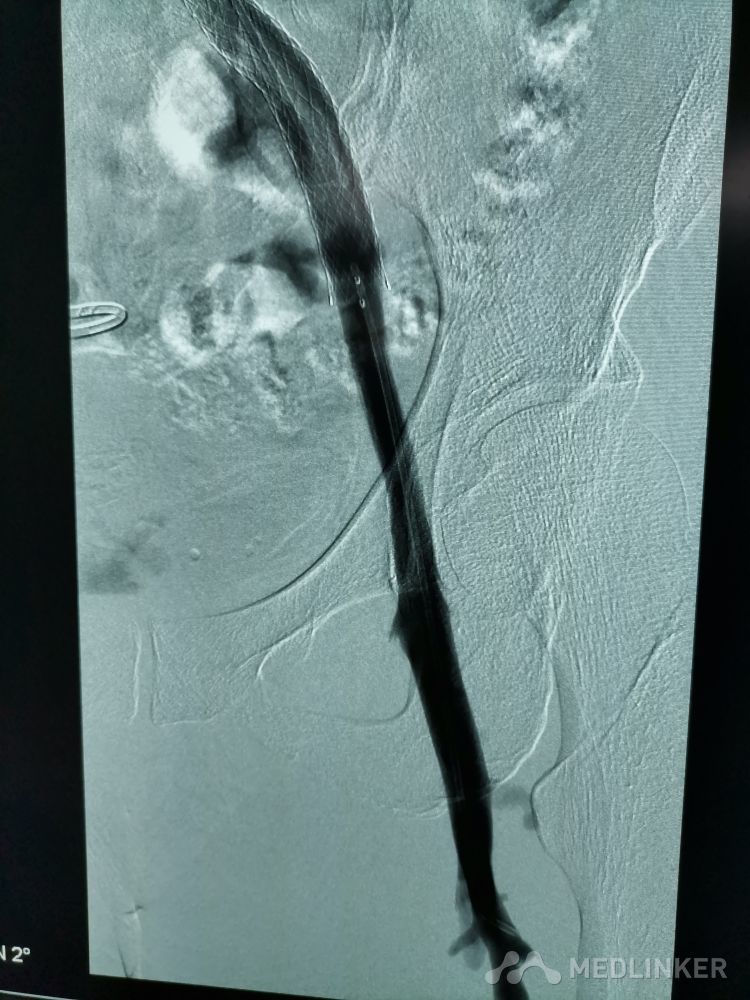

重视髂静脉压迫综合征。不同的临床表现,相同的病因,均为髂静脉压迫所致。第一例,表现为下肢静脉曲张伴溃疡,造影证实,髂静脉支架置入后解决。第二例,表现为左侧髂股静脉血栓,置管溶栓并髂静脉支架置入开通血管。第三例,下肢深静脉血栓后遗症,外院已行髂静脉支架置入,但皮肤营养情况仍持续加重,开通股浅 ,可见病变局部异常坚硬。精准施治,对症下药。